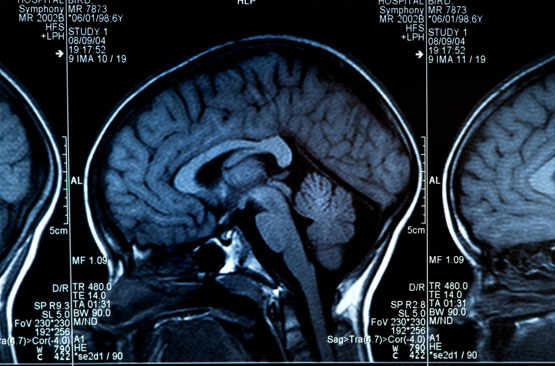

Stopper les tremblements grâce aux ultrasons

Les hôpitaux universitaires de Genève (HUG) proposent une nouvelle méthode pour calmer les tremblements chez les personnes atteintes de la maladie de Parkinson.